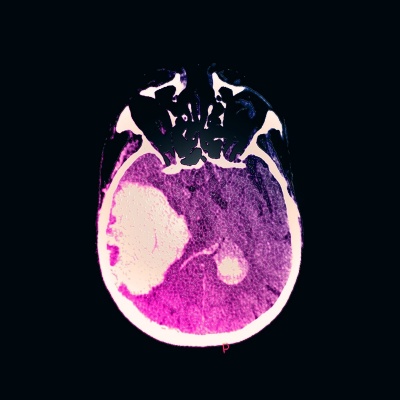

酒を飲み過ぎると血圧が上昇し、肝臓が傷つくことは以前から知られていたが、新たな研究により、脳にも大きな打撃を与える恐れが示唆された。命にかかわる脳出血を引き起こす可能性だ。

米マサチューセッツ総合病院出血リスク・脳卒中予防クリニックのディレクターであるエディプ・グーロル氏のチームが発表した最新の研究結果によると、過度の飲酒をする人は、あまり飲まない人や全然飲まない人に比べて脳出血をより早く発症し、出血量の多さ、脳の損傷の大きさ、致死率の高さなどの点で、より悪い結果になっていたという。